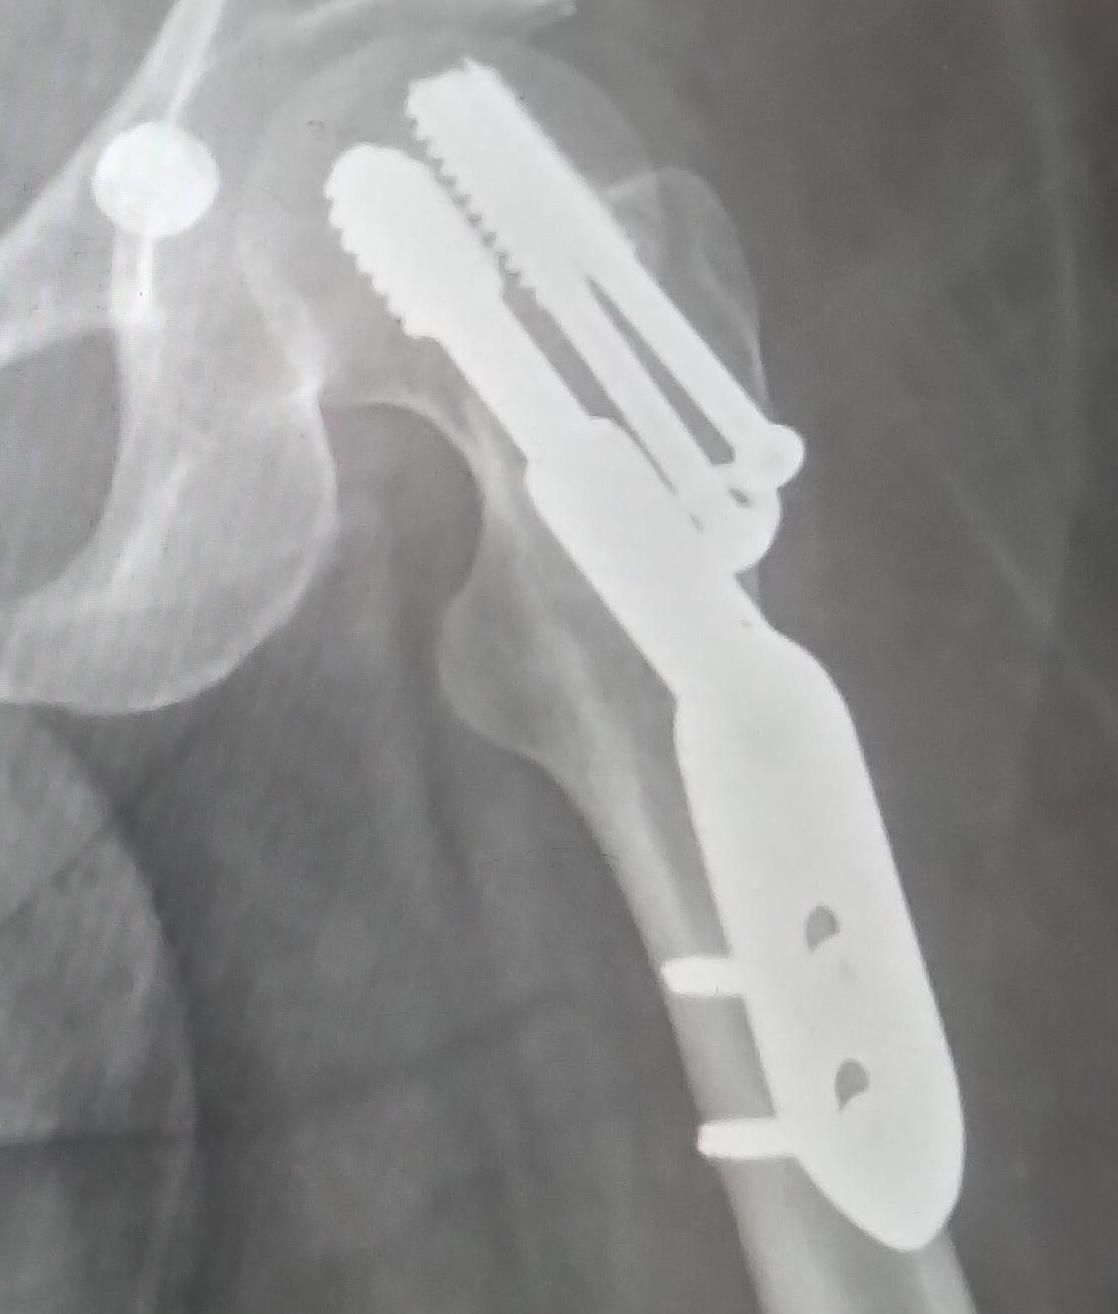

In late July I fell at home and fractured my hip. The operation went well, but given my impairment I don't have the upper body strength to hop out on crutches. I just got home last week after 7 weeks in hospital. Everything's going well and I'm in a much more positive stage of rehabilitation now.

p.s. if you love a good x-ray image, then see the art of my good friend Davey Jose whose paintings and virtual reality film are inspired by x-rays of spinal-cord injuries.